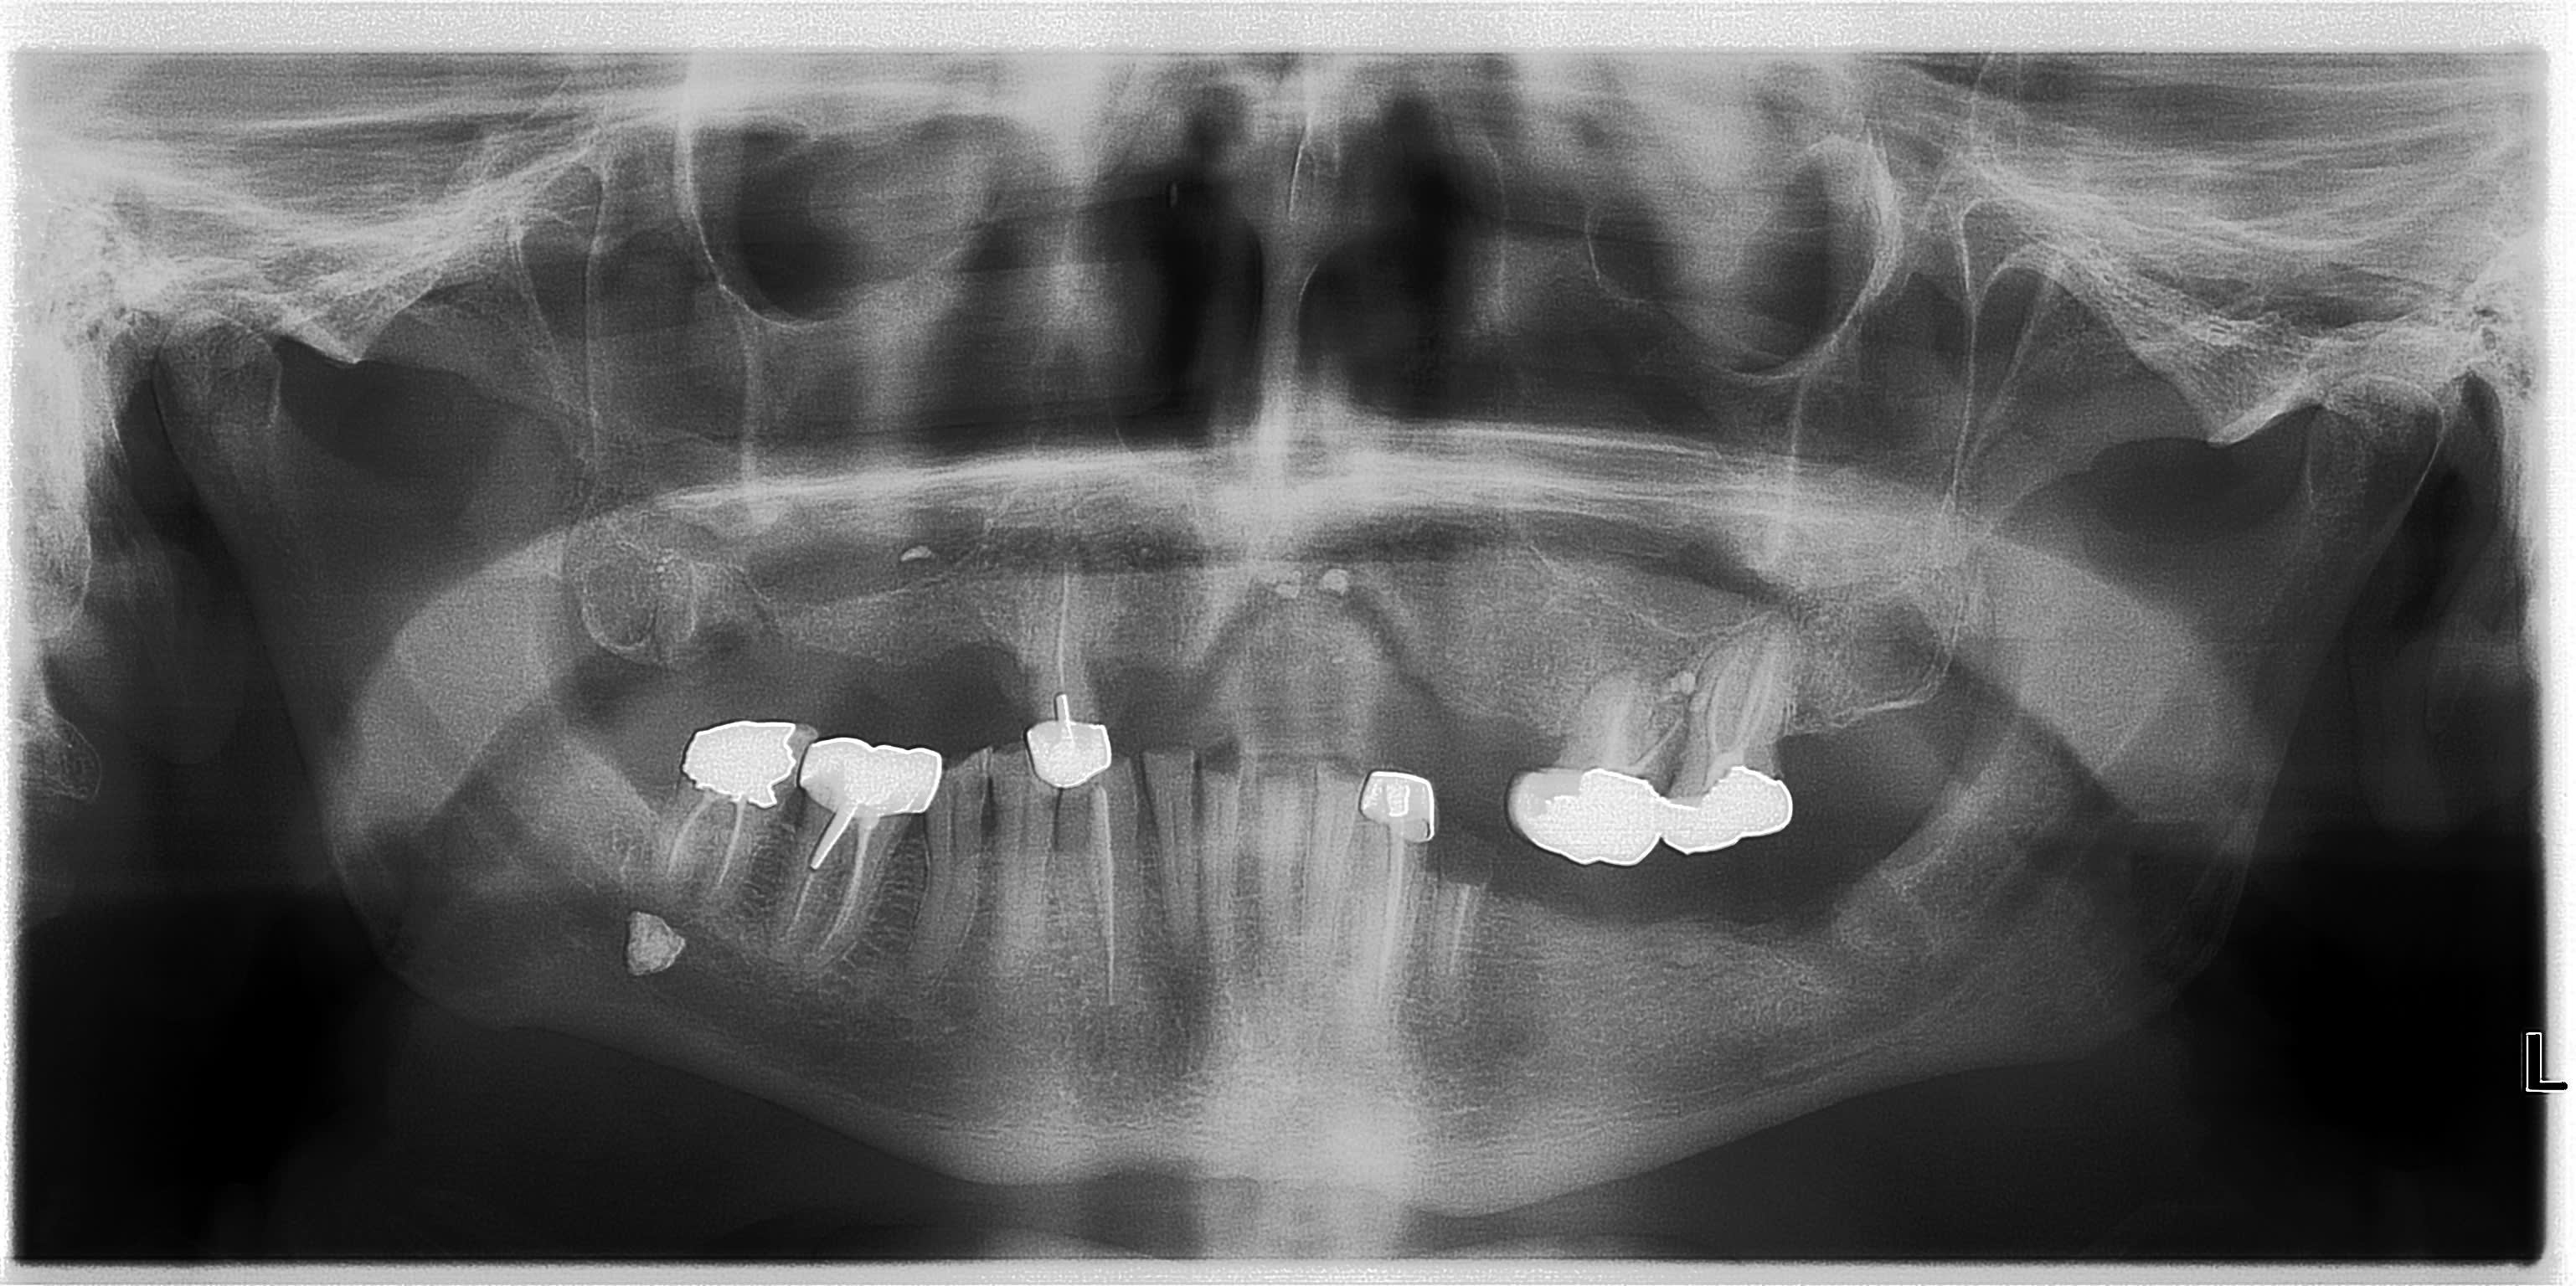

Comme vu à la radio, grosse perte de DV.

Je fais un complet en haut et un stellite en bas après avoir enlevé tout ce qui est douteux (43.45.34 au minimum)

Pourquoi enlever 43.43 et même 35 (à voir) ? couronne RAC 0 avec 47 en prime.

Qu'est-ce que c'est sous la 47 ? Est-ce dans le canal alvéolaire ou est-ce parotidien (peu probable) ?

Lithiase salivaire ? Mais ca me semble trop haut par rapport au plancher.

C'est quoi ce pano merdique non indiqué ? ( attention indu). -)))))

Non avec des antécédents de soins intensifs et une maladie dentaire diffuse c'est un status complet qu'il faut pour y voir clair. Agrémenté d'une empreinte 3 D pour mater l'occlusion. Demande du patient : "j'aimerais bien qu'on me refasse les dents de devant.".